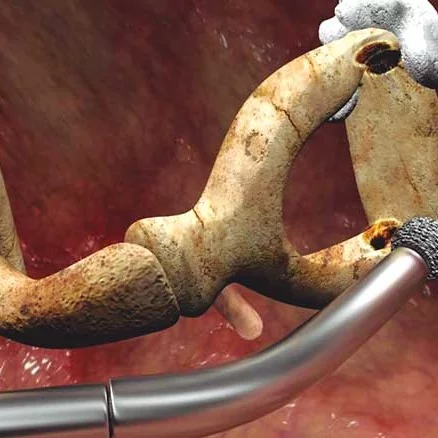

La otosclerosis está causada por un crecimiento anormal del hueso en el oído medio, lo cual desemboca en una pérdida auditiva. Es una patología crónica que provoca esponjosidad en los huesos y la fijación de la base del estribo en la ventana oval.